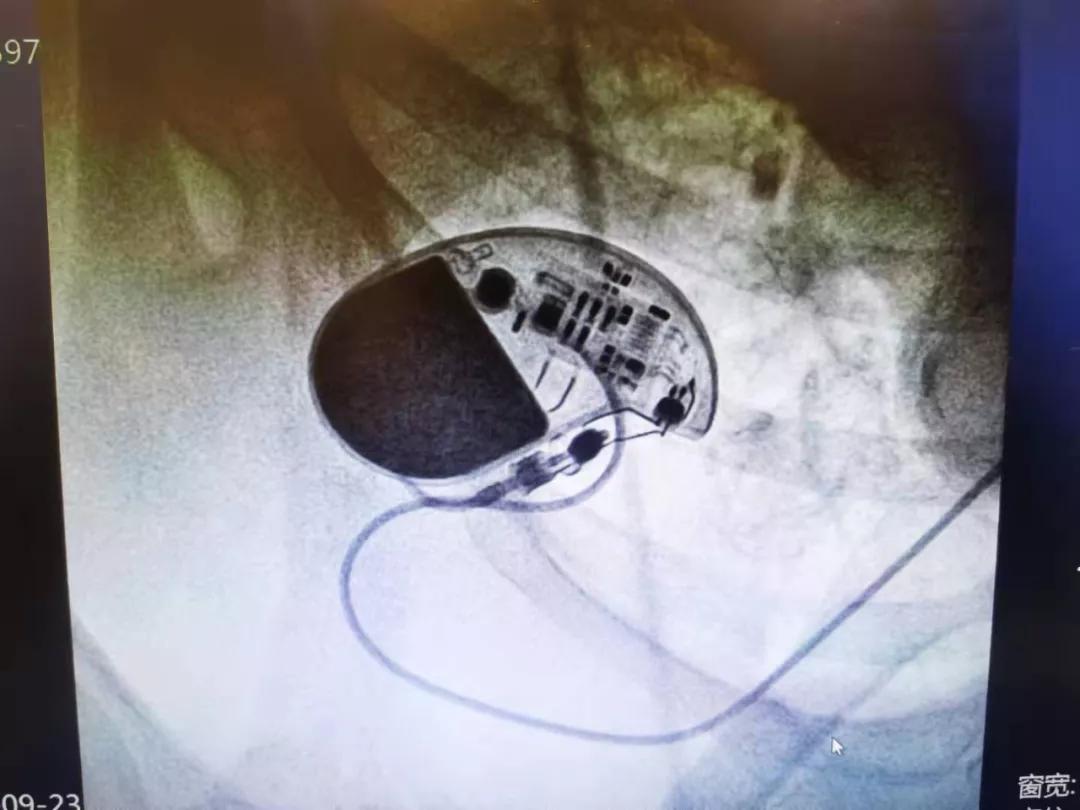

79岁,马上就要迈入耄耋之年了,要在这个年纪再经历一次心脏起搏器手术,更是让人不敢想。9月23日,在太原市中心医院心内科外聘专家马峰的指导下,心内科汾东一病区成功为一位79岁的高龄患者更换心脏永久性起搏器,使老人获得“心”生。

在医护人员的共同努力下,成功为刘阿姨实施了永久性心脏起搏器更换术。整个手术共耗时30分钟,术中出血量少。术后,在医护人员的精心呵护下,刘阿姨无任何并发症,患者家属对医院心内科手术团队严谨、快捷、高效、安全的操作表达了深深的谢意。

心脏起搏器是一种植入于体内的电子治疗仪器,通过脉冲发生器发放由电池提供能量的电脉冲,通过导线电极的传导,刺激电极所接触的心肌,使心脏激动和收缩,从而达到治疗由于某些心律失常所致的心脏功能障碍的目的。其工作原理是脉冲发生器定时发放一定频率的脉冲电流,通过导线和电极传输到电极所接触的心肌(心房或心室),使局部心肌细胞受到外来电刺激而产生兴奋,并通过细胞间的缝隙连接或闰盘连接向周围心肌传导,导致整个心房或心室兴奋并进而产生收缩活动。